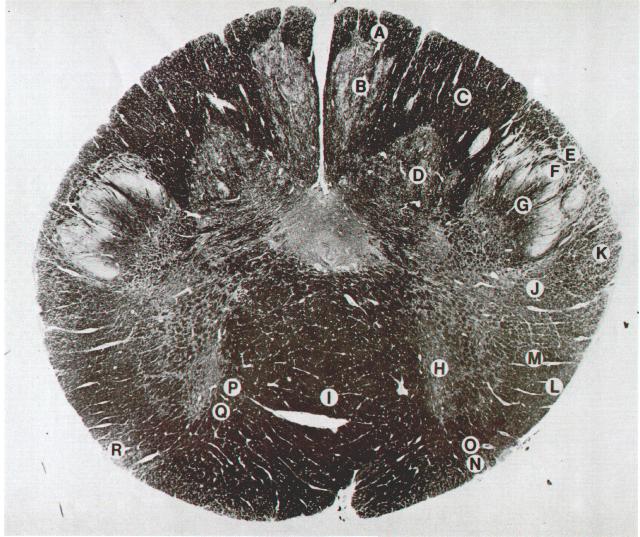

Plate VI. Medulla oblongata at the rostral level of the pyramidal decussation

A. Gracile fasciculus

B. Gracile nucleus

C. Cuneate fasciculus

D. Cuneate nucleus

E. Spinal trigeminal tract

F. Pars gelatinosa of spinal trigeminal nucleus

G. Pars magnocellularis of spinal trigeminal nucleus

H. Accessory nucleus

I. Pyramidal decussation

J. Rubrospinal tract

K. Dorsal spinocerebellar tract

L. Ventral spinocerebellar tract

M. Lateral spinothalamic tract

N. Anterior spinothalamic tract

O. Lateral vestibulospinal tract

P. Medial longitudinal fasciculus

Q. Tectospinal tract

R. Spino-olivary tract